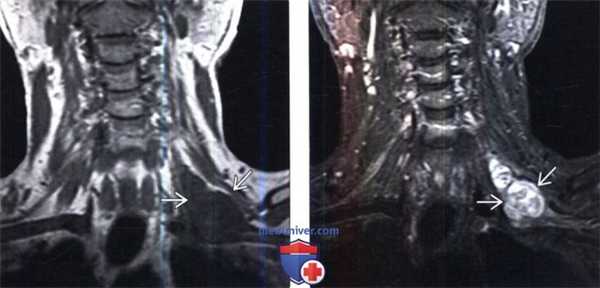

(Слева) На фронтальном Т1-ВИ пациента с НФ1 визуализируется крупная ЗООПН верхнего средостения и нижней части шеи, окружающая собой левую подключичную артерию и инфильтрирующая левое плечевое сплетение.

(Справа) На аксиальном Т1-ВИ с КУ у этого же пациента визуализируется крупная накапливающая контраст ЗООПН верхнего средостения, смещающая трахею вправо, окружающая левую подключичную артерию и распространяющаяся в левую надключичную ямку. Центральная неправильной формы зона, не накапливающая контраст, является участком некроза опухоли.